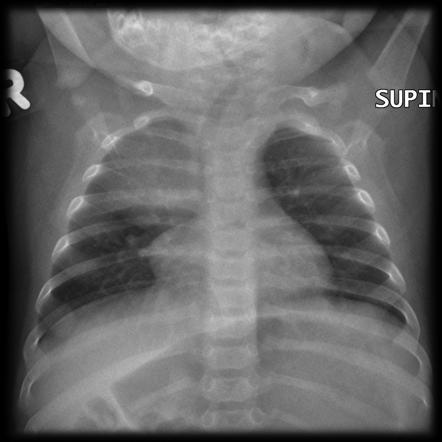

O sinal do “barco à vela” na radiografia pode ser confundido com um infiltrado pneumônico na criança. O que esse sinal quer dizer?

Timo (aspecto triangular ou lobulado).

Pneumonia: a radiografia de tórax* *não é necessária* naquelas crianças que *não* apresentem *s_in_ais de gravidade e que não serão internadas.

Solicitar: Raio X